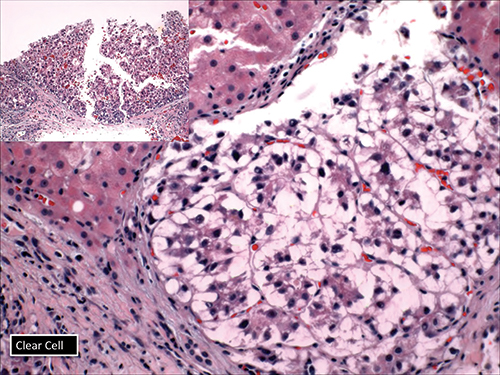

Dr. Richards also displayed the clear cell variant of HCC (Fig. 8), which she said might be confused with metastatic renal cell cancer or something else. “But be aware that you can have clear cell features in many carcinomas, including cholangiocarcinoma.”